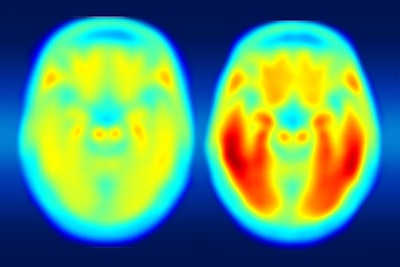

With the help of a new PET imaging agent, researchers at Washington University in St. Louis have shown how tau protein deposits in the brain are better indicators of a person's likely progression to Alzheimer's disease than beta amyloid, according to a study published May 11 in Science Translational Medicine.

Called T807, the PET radiopharmaceutical is cleared for clinical trials and is offering early evidence that could prove beneficial in imaging for cognitive impairment by binding to tau protein.

Measures of tau in the cerebrospinal fluid correlated with tau deposition in the temporal lobe as seen with PET, the researchers found. In addition, the presence of tau protein in the temporal lobe more closely matched dementia status and better predicted cognitive performance than beta-amyloid deposits in any region of the brain.

The results suggest that a person can tolerate a certain amount of tau in the hippocampus, but when it begins to spread to other areas, especially the lateral temporal and parietal lobes, that advance can be the catalyst for progression to Alzheimer's disease, according to Ances.